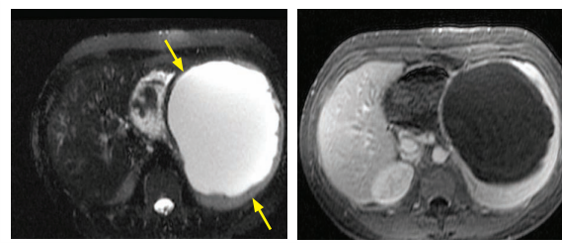

MRI characteristics of splenic hemangiomas

T2 bight enhancement peripherally or homogenously